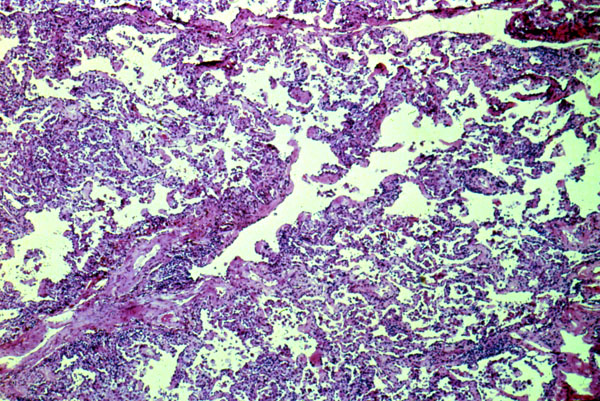

Hypersensitivity pneumonitis is an immunologic reaction to inhaled antigens. This slide shows a chronic interstitial pneumonitis with many lymphocytes with a peribronchiolar accentuation.